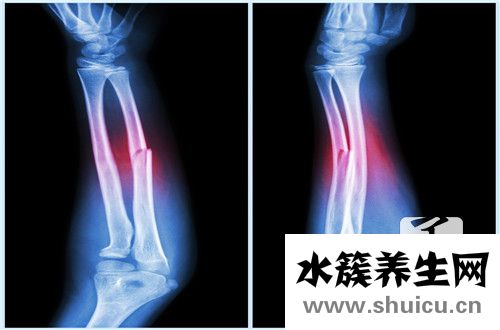

尺骨和radius骨是人體上臂骨骼的一部分。 運輸較為重物時,每個人都有可能發生尺骨骨折和radius骨骨折等情況。 這種情況對身體有很大的影響。 較為 較為做居中中的許多事情很不方便。 為了應對尺...